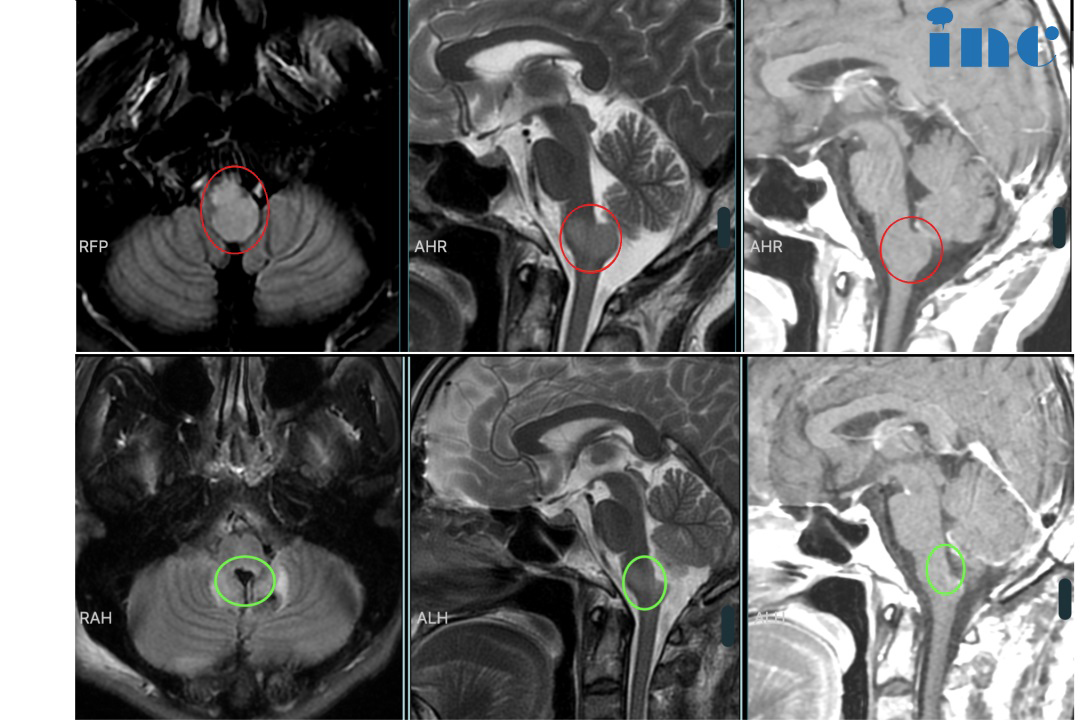

21 岁的张远早在6年前就检查出无症状脑积水,当时由于没有症状,一直进行保守治疗。2018 年底,正在读大学的张远突然出现剧烈头痛伴呕吐症状。反复头痛已经严重影响到正常的学习和生活,在19年进行了脑脊液分流术,术前磁共振检查提示中脑导水管狭窄,但并未发现占位性病变,分流术后症状消失。

然而,直到2021 年 2 月,张远再次出现剧烈头痛伴呕吐,并有眼球向上运动困难,分流管调压后症状消失。

更可怕的是,于当地医院行颅脑磁共振检查,检查结果令医生大吃一惊。提示中脑顶盖占位性病变,较大直径约8mm。但是对于这个位置,当地医生也表示无法手术……

2022 年 8 月张远病情再次加重,眼球活动受限,眼球向下运动困难,后脑勺偶然还会感到麻木或疼痛。复查磁共振提示肿瘤增大,此时肿瘤较大直径12mm,一年半内生长4mm。

然而,这个肿瘤不曾停止生长,2022 年 10 月复查核磁提示肿瘤增大,自行测量肿瘤大小约 18mm,两月内竟激增6mm!

肿瘤正以惊人的态势恶化,再拖下去,纵使是巴教授这样的颅底肿瘤教授,也无法为其手术。在咨询巴教授得到了“病人不能等太久”“手术目的是完全(全切)或几乎完全(98-99%)切除肿瘤”的答案后,他们决定争取2022年巴教授中国示范手术的机会。

2022年12月3日,张远于苏州市独墅湖医院接受巴教授主刀的手术,实现近全切。

术后3个月复查磁共振未见明显复发,达到较大水平功能保护前提下影像学全切。